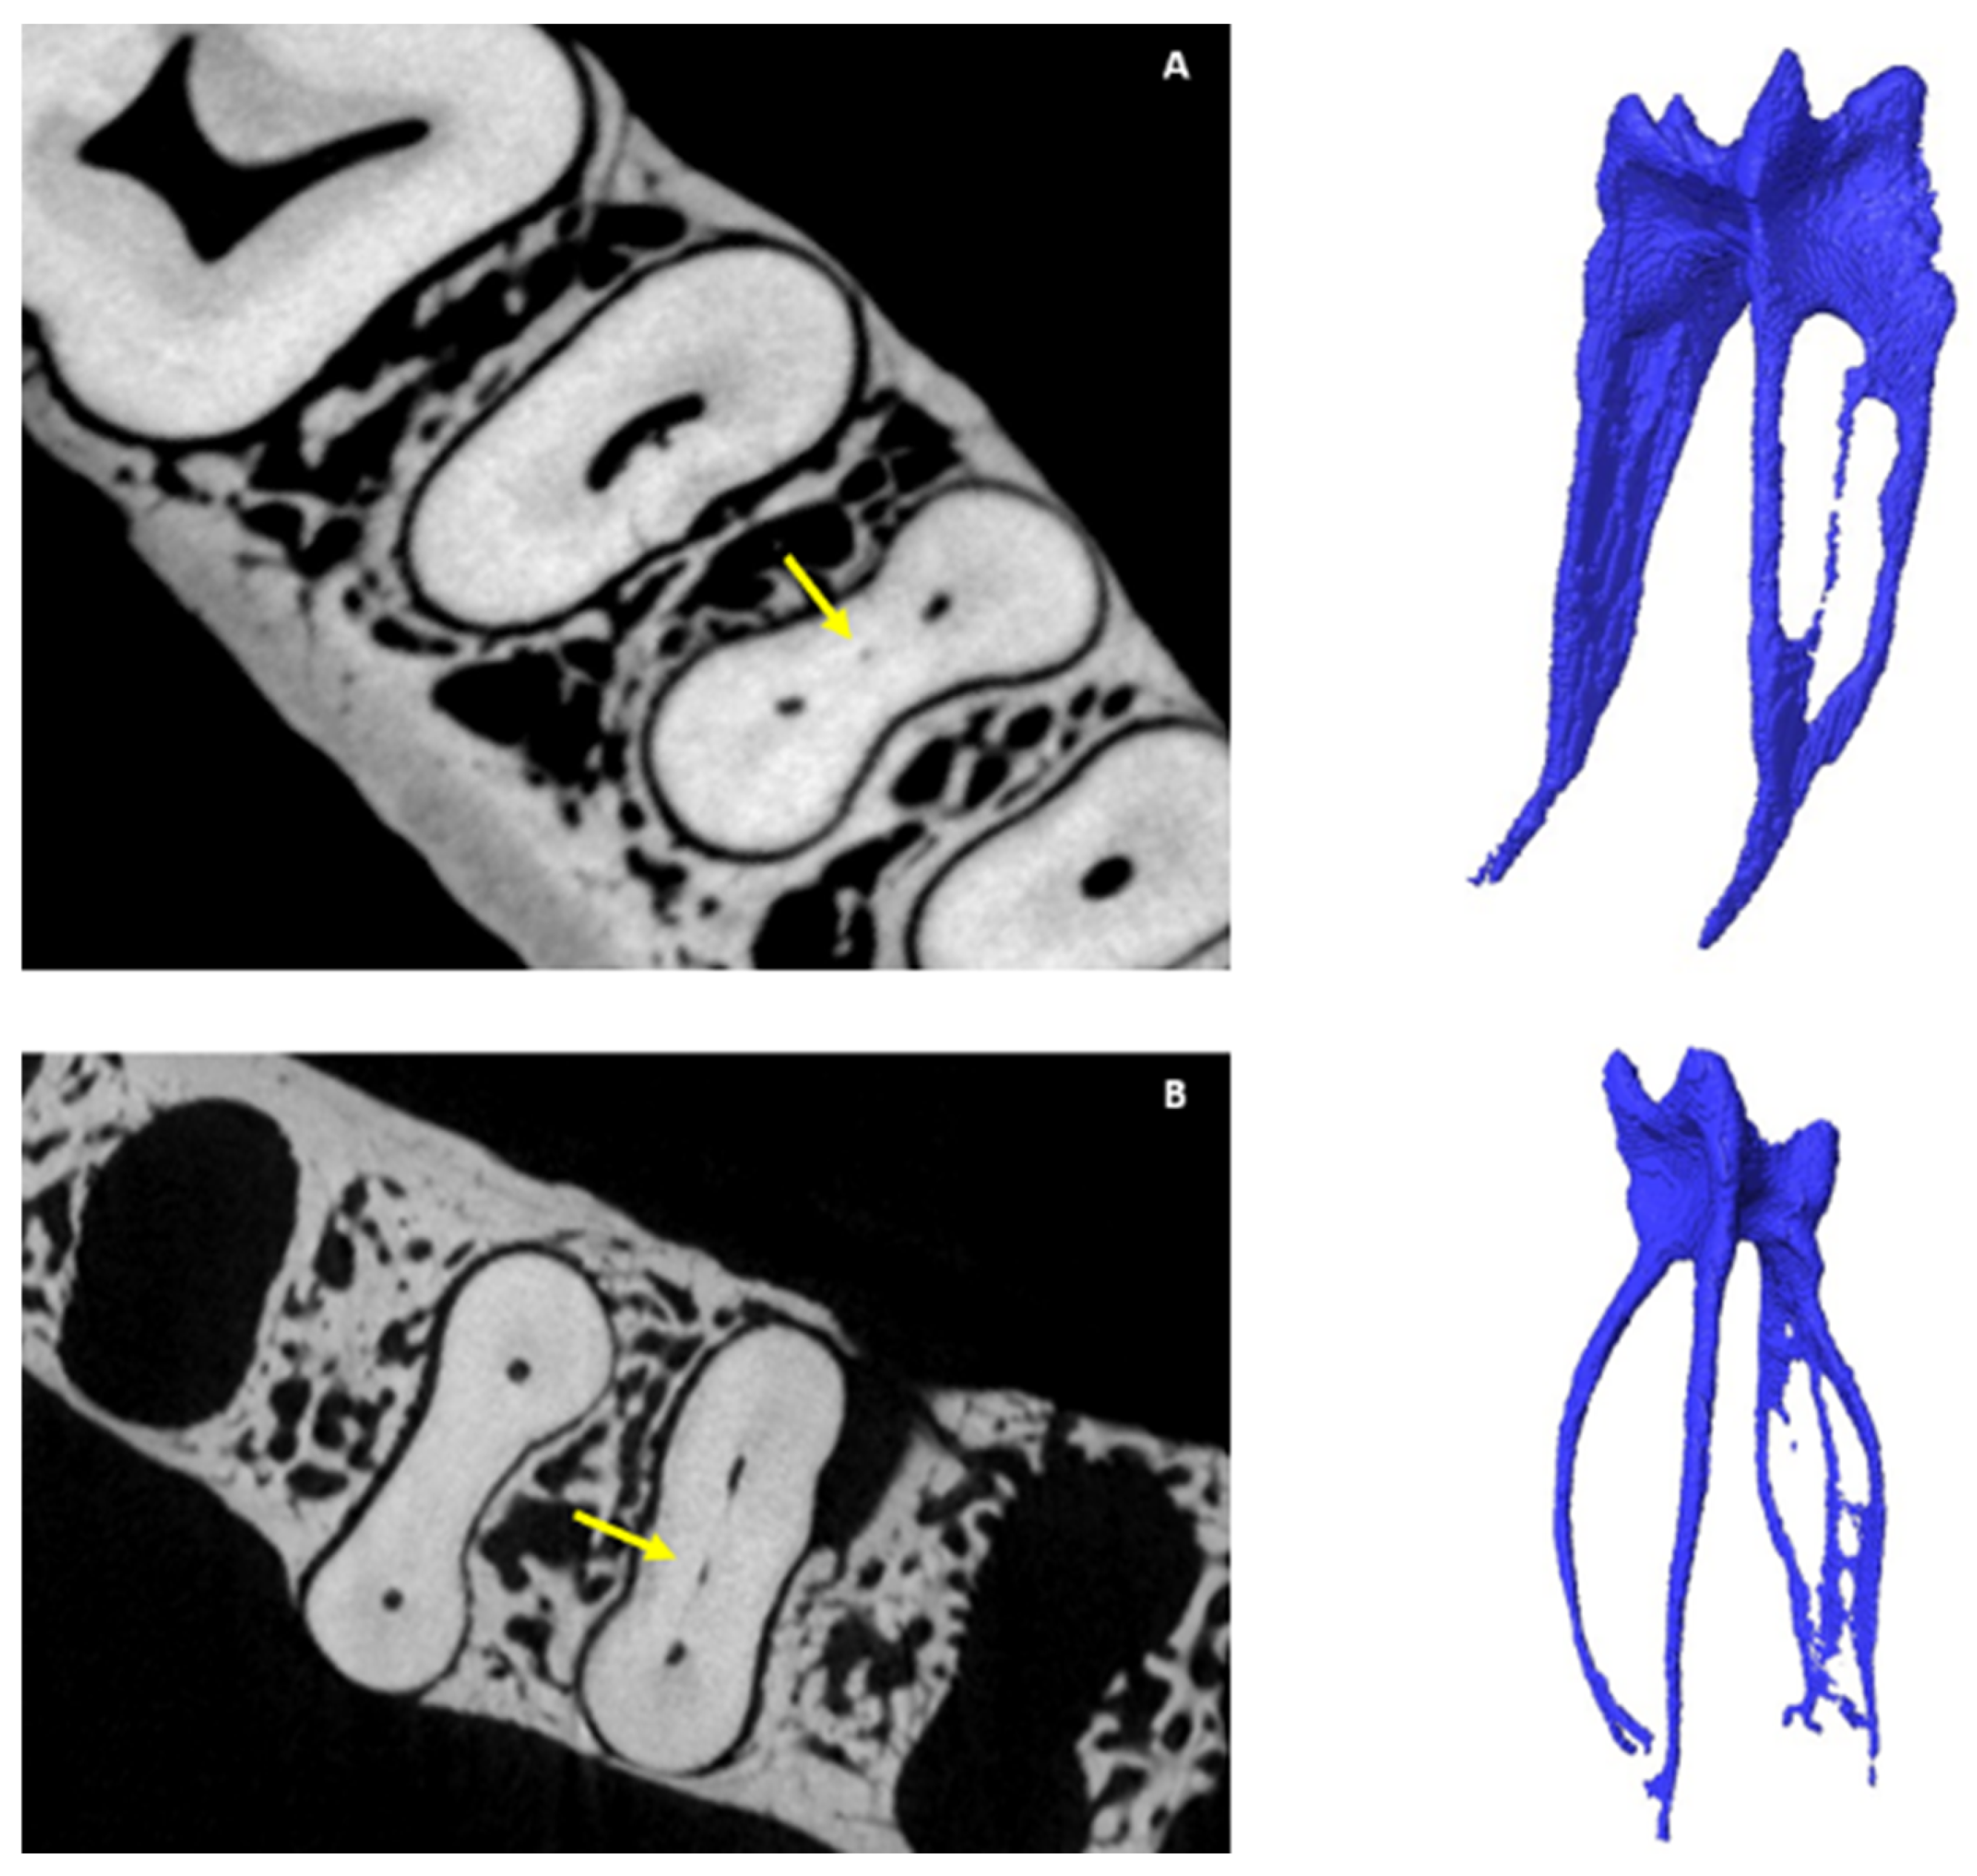

3.3. Number of Canals per Root

3.4. Chamber Canals

3.5. Accessory Canals (ACs)

3.5.1. M Root

3.5.2. D Root